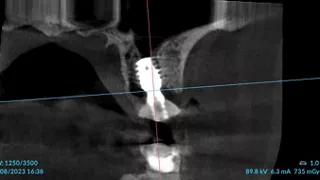

3a. 3b. 3c. 3D volumetric diagnosis and planning of implant therapy.

3a

3b

3c

4. Radiograph exhibiting a suitable septum for immediate implant placement.

4